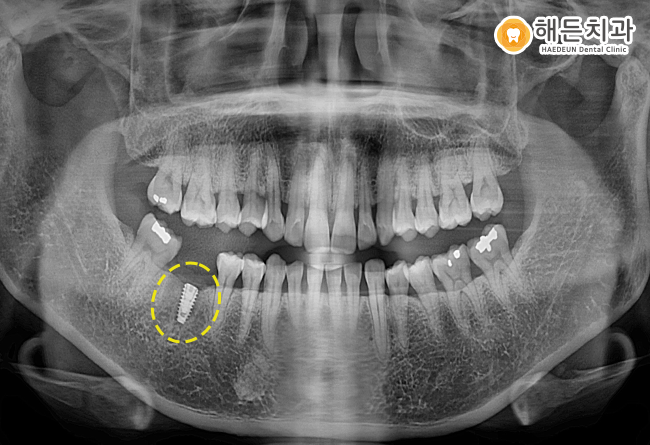

과거 신경치료 및 크라운 치료를 받았던

오른쪽 아래 첫번째 큰 어금니를 발치하고,

임플란트를 식립한 후 파노라마 사진입니다.

우선 파노라마 사진을 보시면,

임플란트의 치아 뿌리 역할을 하는

픽스처만 식립되어 있는 상황인데요.

사전에 계획하였던 임플란트의 식립 위치 및 방향,

각도 등에 맞도록, 잘 식립이 되었답니다. 👍